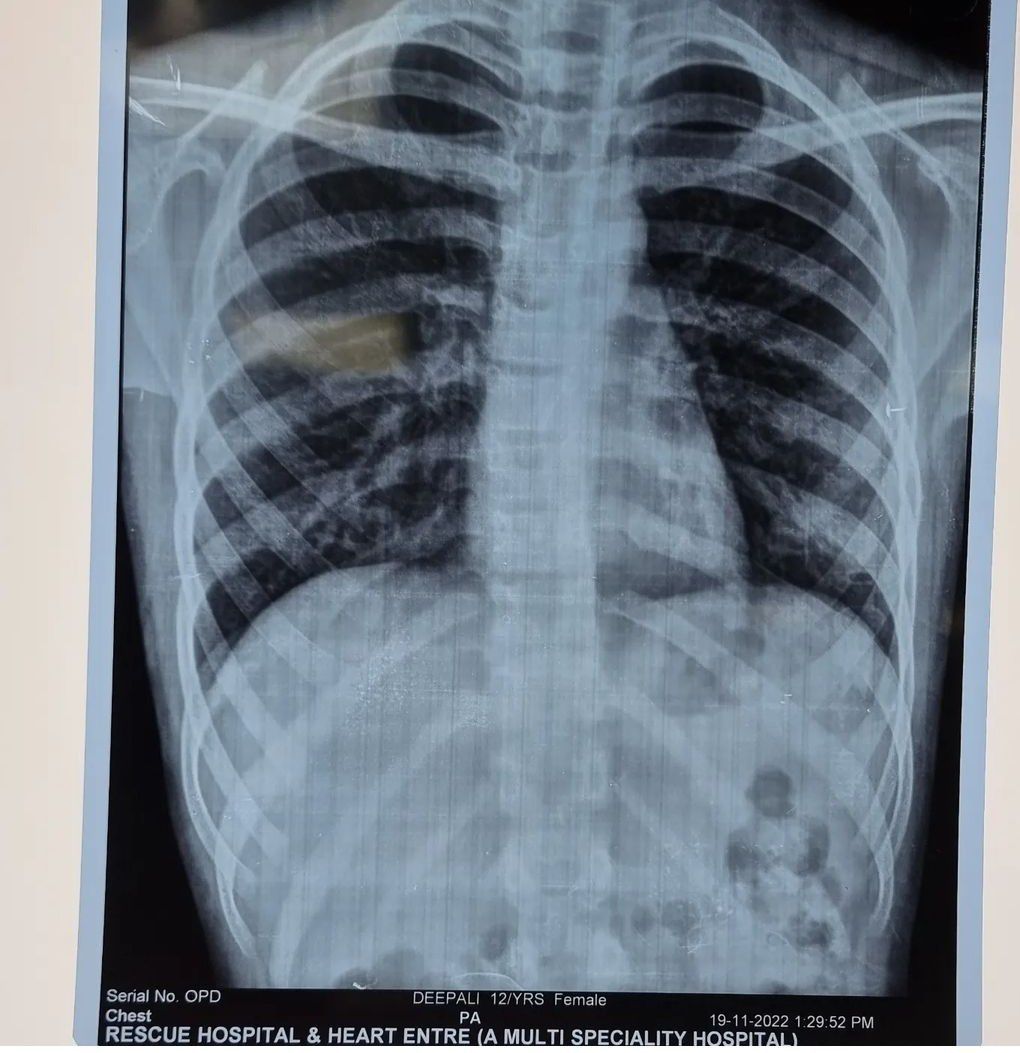

Diagnose the patient from the given radiograph.

What are the cheif compalints of the patient ?? Left heart border seems to be straighten 1. Juvenile Mitral stenosis 2. Improper flim posture